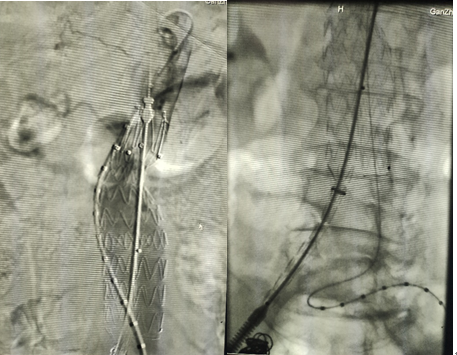

4、根據(jù)3D打印血管模型輔助支架放置的位置。右股動(dòng)脈入路導(dǎo)入支架主體,分支導(dǎo)絲引出體外,腹主動(dòng)脈段部分釋放

5、造影調(diào)整支架位置,調(diào)整導(dǎo)絲纏繞問(wèn)題,注意左右腎動(dòng)脈的位置關(guān)系

6、造影明確后釋放支架主體;注意力度及方向